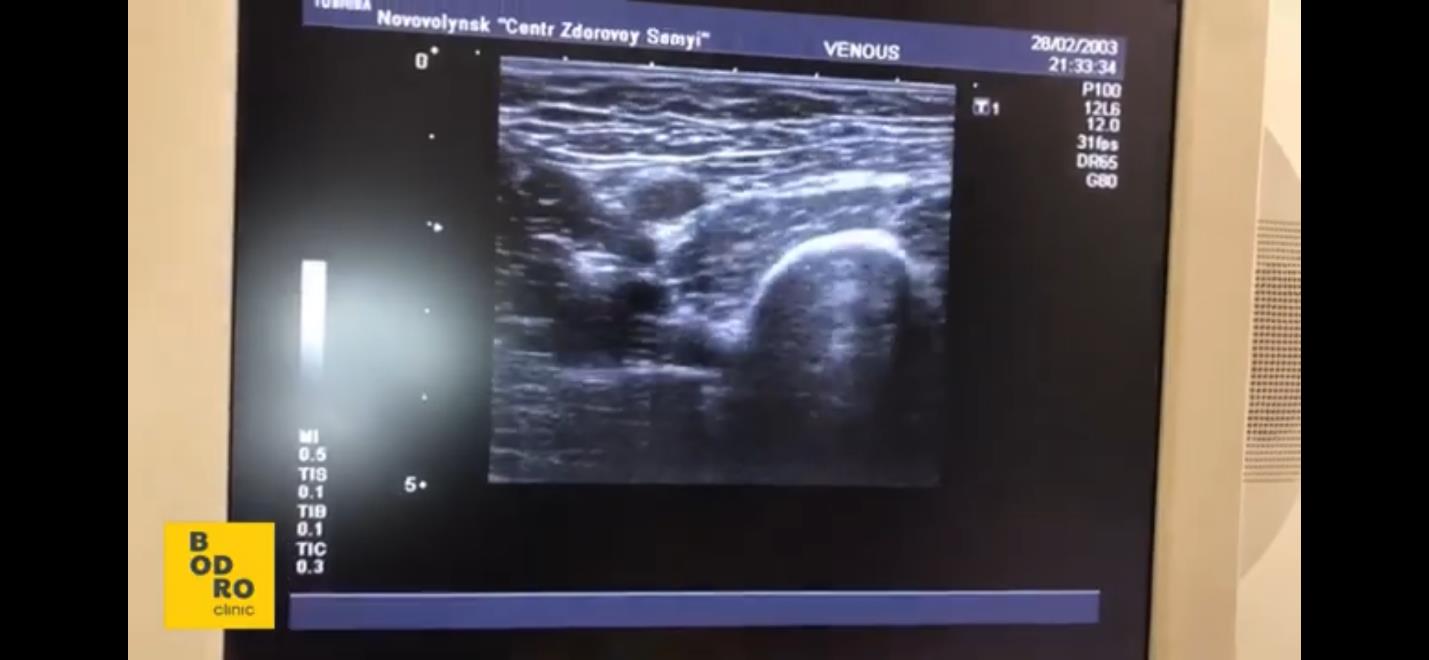

Усе дуже просто. Безпосередньо на консультації проводжу УЗД вражених судин, оцінюю фізіологічний стан пацієнта, чи є надмірна вага. Цікавлюся способом життя, активно живе людина чи ні, раціоном харчування та сферою діяльності. Але ключовий фактор, який беру до уваги, – чи є в людини венозна недостатність.

Це чітко бачу під час УЗД й оцінюю складність оперативного лікування та ризики.Визначення анатомії вен нігВизначення вени, через яку йде неправильний кровотікМаркування місця, де перекриваємо вену для правильного кровотоку